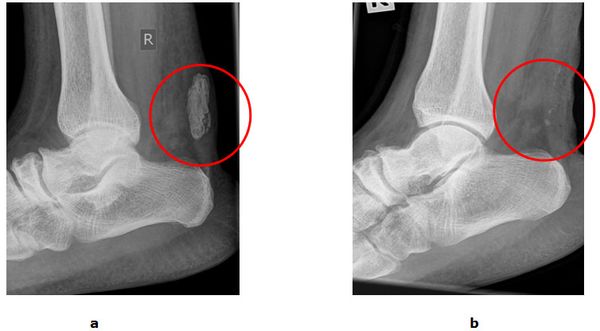

Abb.2: a Großer Kalkherd in der Sehne. b Röntgenbild nach der operativen Entfernung unter Erhalt der Sehne.